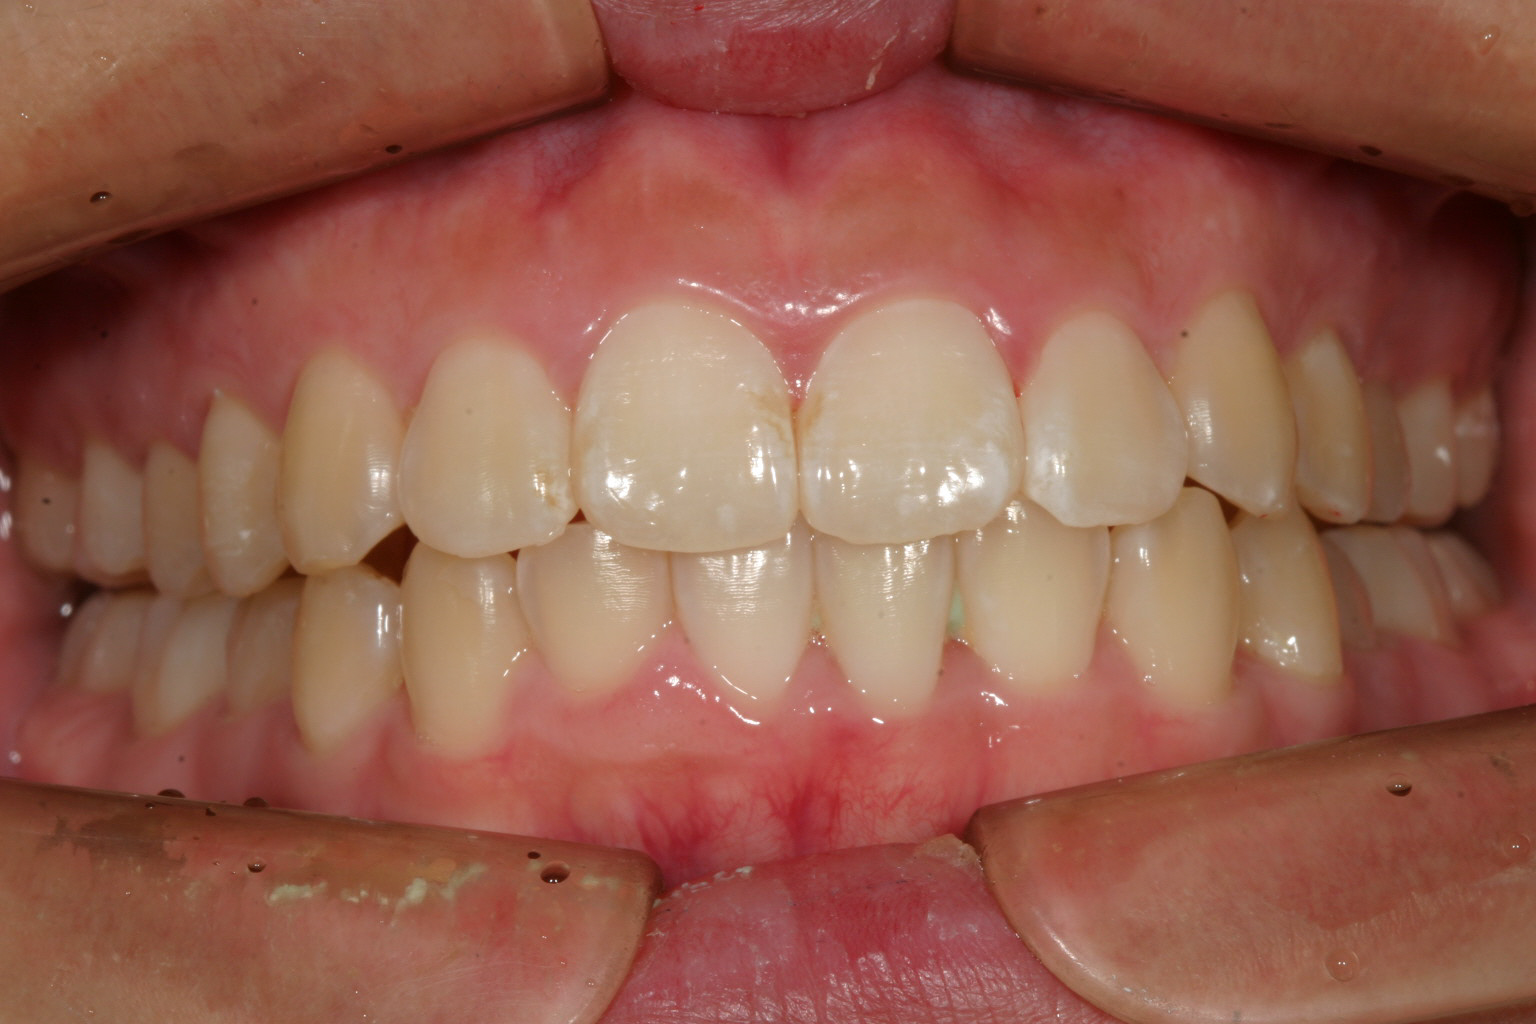

術前と比べるとだいぶ前歯が引っ込みました。

下顎前歯も綺麗に配列し前突感も無くなりました。